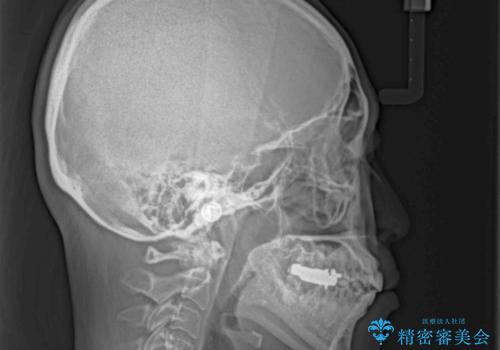

極端な上下前歯の開咬を改善 オープンバイトのインビザライン矯正

治療前に、いくらインビザライン矯正がオープンバイトを得意としているとは言え、さすがに限界があるだろうと思っておりましたが、前歯でレタスが噛めるまで改善することができました。

顔の印象も大きく変わり、患者様には大変満足していただきました。